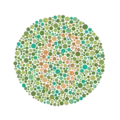

The test consists of a number of Ishihara plates, each of which depicts a solid circle of colored dots appearing randomized in color and size.[3] Within the pattern are dots which form a number or shape clearly visible to those with normal color vision, and invisible, or difficult to see, to those with a red-green color vision defect. Other plates are intentionally designed to reveal numbers only to those with a red-green color vision deficiency, and be invisible to those with normal red-green color vision. The full test consists of 38 plates, but the existence of a severe deficiency is usually apparent after only a few plates. There are also Ishihara tests consisting of 10, 14 or 24 test plates, and plates in some versions ask the viewer to trace a line rather than read a number.[4]

- Vanishing plates: only individuals with normal color vision could recognize the figure.

Ishihara Plate No. 1 (12) Ishihara Plate No. 13 (6)

Ishihara Plate No. 13 (6) Ishihara Plate No. 23 (42)